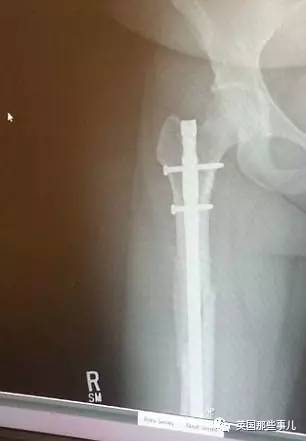

在那场车祸中,

Audra的鼻子被迎面甩过来的脚弄伤,

她的脚踝,

股骨的四个部分也被弹出的气囊硬崴至骨折...…

她的脚踝、臀部、膝盖上分别被打上了2个钢钉…